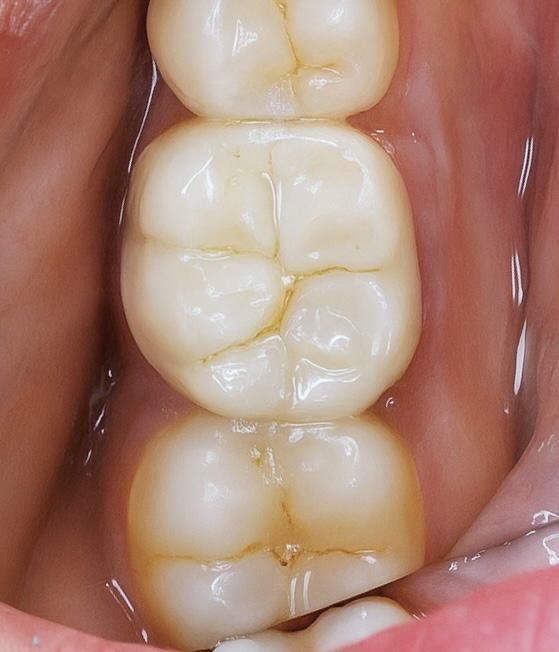

- Tooth prepared conservatively for full coverage.

- Definitive crown fabricated in monolithic zirconia for strength and longevity.

- Bonded with resin cement under isolation.

- Occlusion refined to preserve functional harmony.

Follow-Up – 1 Year

- Soft tissue response healthy and stable.

- Patient asymptomatic, full function restored.

- Restoration clinically intact with excellent marginal integrity.